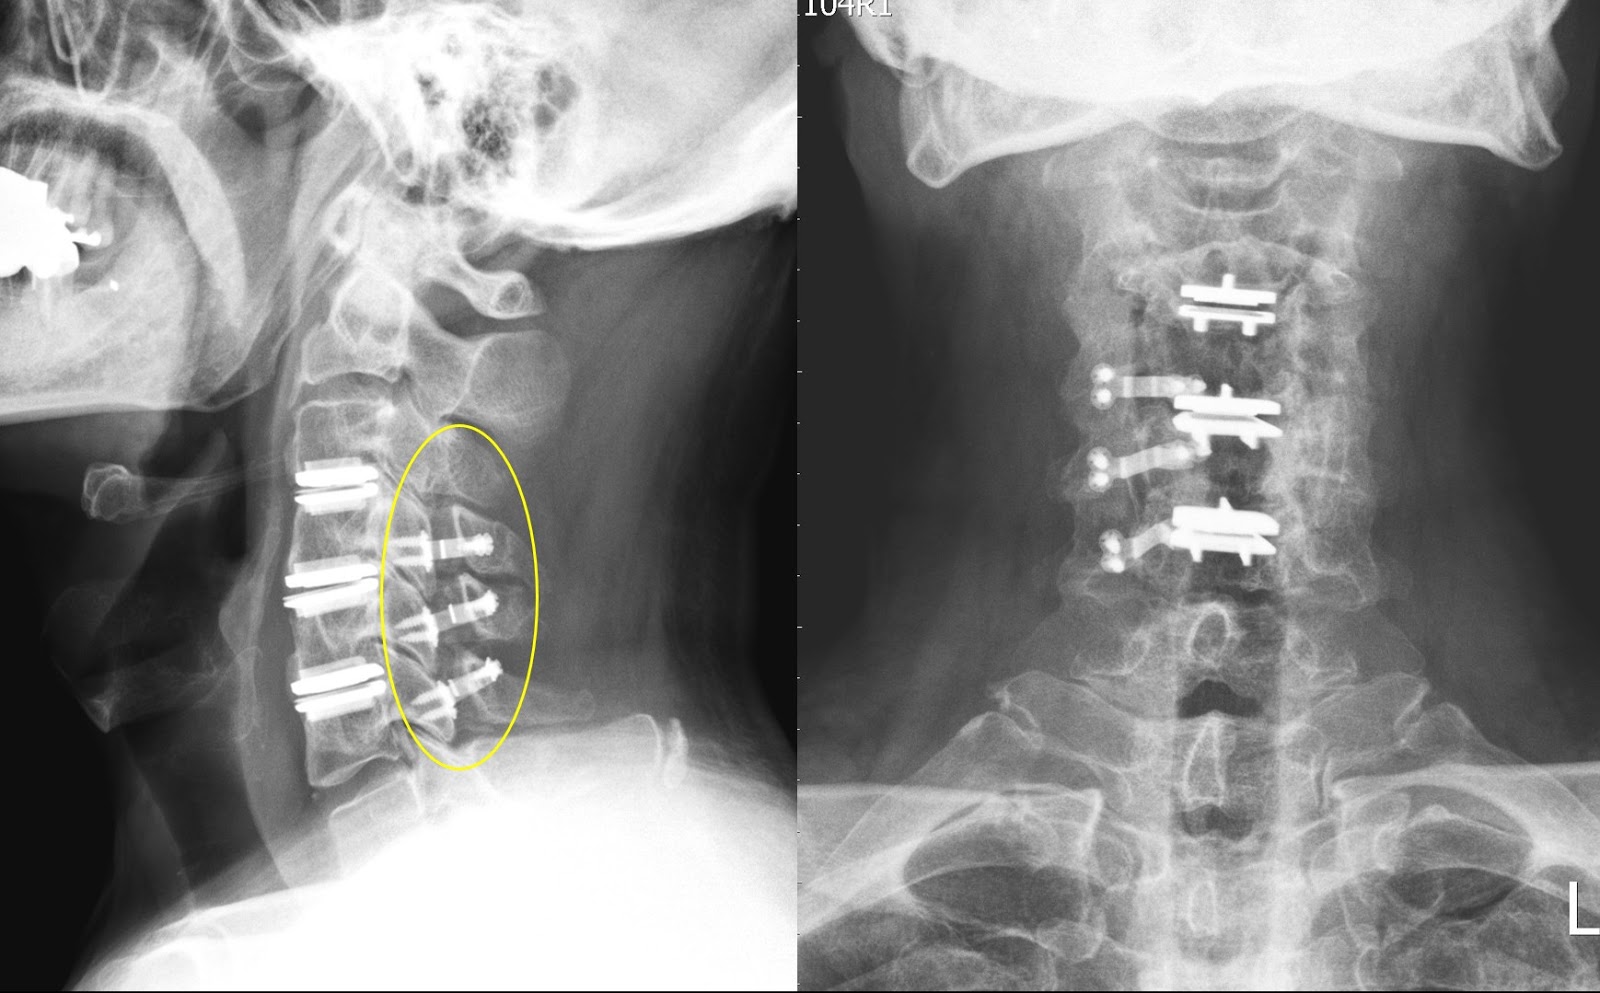

LateOnset Esophageal Perforation After Salvage Anterior Cervical Spine